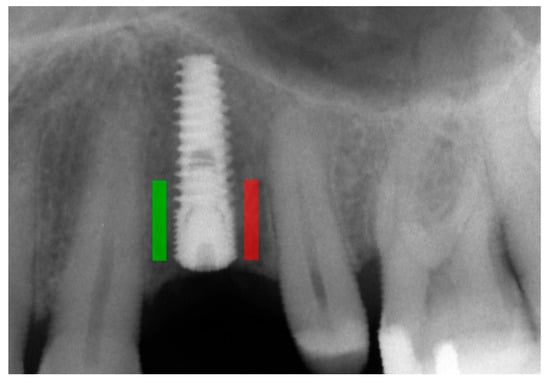

Marginal bone loss (MBL) was measured on radiological images [11] (Figure 1). The texture of X-ray images was analyzed using MaZda 4.6 freeware developed by the University of Technology in Lodz [6,12] to assess measures of corticalization in the peri-implant environment of trabecular bone (representing original bone before implant-related alterations) and soft tissue (indicative of marginal bone loss). MaZda provides both first-order (Mean Optical Density) and second-order (Differential Entropy: DifEntr; Long-Run Emphasis Moment: LngREmph) data. As the second-order data are provided for four directions in the image and the present study did not focus on directional features, the arithmetic mean of these four primary data points was used for further analysis. Regions of interest (ROIs) were marked near the neck area (Figure 2) and normalized (μ ± 3σ) to have the same mean (μ) and standard deviation (σ) of optical density within the ROI. To further reduce noise, data were limited to 6 bits. For analysis in a co-occurrence matrix, a spacing of 5 pixels was chosen. In the formulas that follow, p(i) is a normalized histogram vector (i.e., histogram entries divided by the total number of pixels in the ROI), i = 1, 2, …, and Ng denotes the number of optical density levels. The Mean Optical Density feature (a first-order feature) was calculated as follows:

Figure 2. Marking an ROI. ROIs were marked near the implant neck area. Green area—mesial implant neck area; red area—distal implant neck area. Abbreviations: ROI—region of interest.